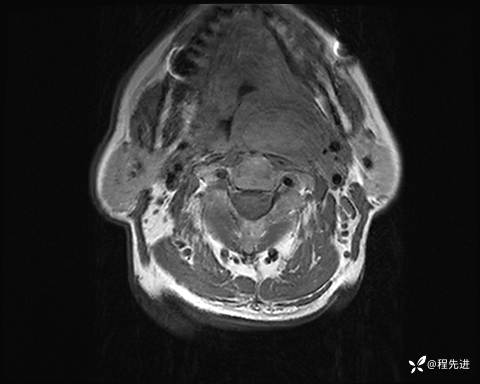

MRI平扫+增强:

T2压脂: